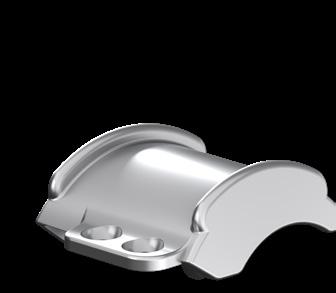

COMPONENTS

• 3-component, non-constrained mobile-bearing design offering four degrees of freedom.

• Anatomic components + UHMWPE insert sizes in 4 thicknesses for precise fit and reduced stress.

• Titanium plasma & hydroxyapatite coatings on tibial/talar implants for uncemented fixation.